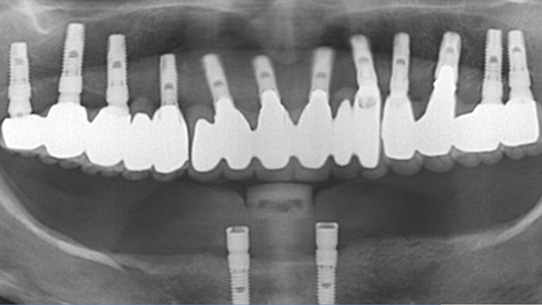

상악틀니를 사용 중 저작력이 약한 환자분. 대학병원에서 전체 임플란트를 받으시려 했으나 비용 문제로 고운미소로 내원하셨습니다.

당뇨수치가 있어 내과와 연계하여 식생활 조절과, 운동, 인슐린 치료를 병행하여 충분한 혈당관리를 하고

임플란트 수술을 시행하였습니다.

임플란트를 지지하기 위한 뼈의 상태가 좋지 않아, 상악동 뼈 이식과 함께 총 24개의 임플란트를 식립하였습니다.

전체 임플란트가 완성된 이후에도 내과와 지속적인 연계로 전신건강이 회복될 수 있게 노력해야 합니다.